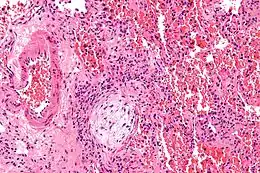

Micrographie montrant un corps de Masson (excentré à gauche/en bas de l'image - circulaire pâle et paucicellulaire), tel qu'on peut l'observer dans la pneumonie organisatrice cryptogénique. Le corps de Masson obstrue les voies respiratoires. L'artère associée à la voie respiratoire oblitérée est également visible (à l'extrême gauche de l'image). Coloration à l'hématoxyline et à l'éosine.